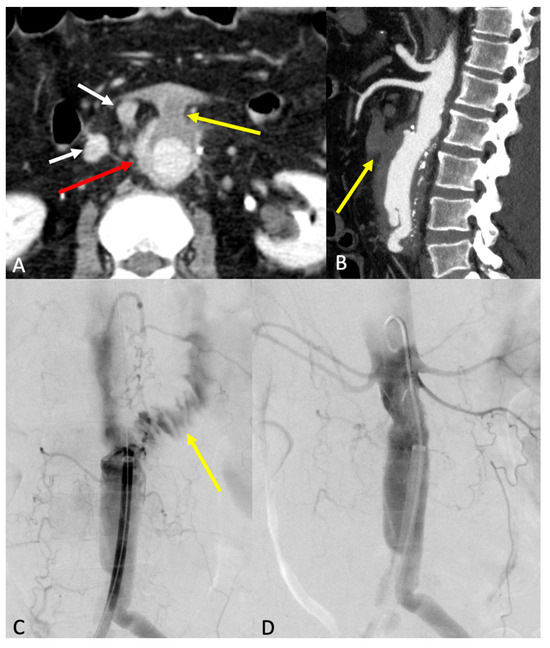

7.3. Endoleak

- Type 1 endoleaks involve direct blood flow into the aneurysm sac due to insufficient seal at the stent graft’s proximal or distal attachment zones. It poses a high risk of rupture and occurs at three possible locations: type 1a, due to inadequate seal at the proximal end; type 1b, due to distal end inadequacy; and type 1c, which occurs at an iliac occluder following aorto-uni-iliac (AUI) repair with femorofemoral crossover graft.

- Type 2 endoleaks: the most common form, arising from collateral vessel backflow, especially from lumbar arteries or the inferior mesenteric artery (IMA). Risk factors include the presence of patent aortic side branches, IMA diameter over 3 mm, patent lumbar arteries (more than three, or over 2 mm in diameter), and anticoagulant use. Embolization of these vessels or non-selective sac embolization can reduce the occurrence of type 2 endoleaks.

- Type 3 endoleaks: these result from stent graft component separation or a tear in the graft fabric. Causes include stent graft migration, inadequate overlap between components (Type 3a), or material fatigue (Type 3b). Component separation can precede the development of an endoleak.